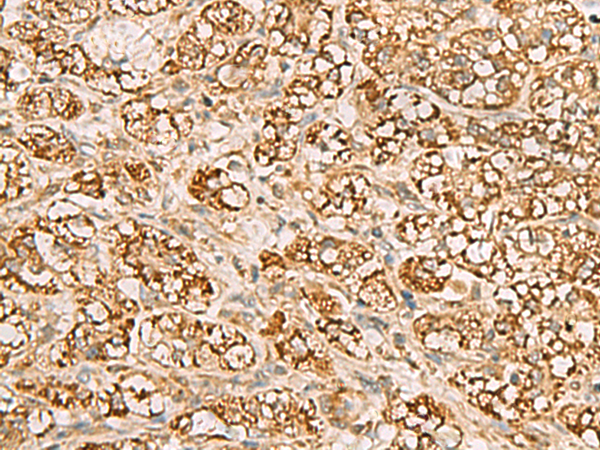

ELISA, IHC

IHC positive control:

Human liver cancer

IHC Recommend dilution:

50-200